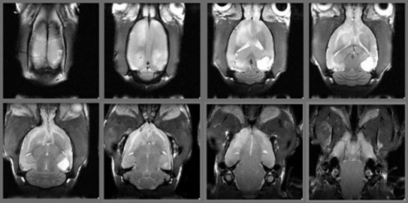

fMRI、Resting state fMRIの例

小動物のfMRI

ラットのDMN(Default Mode Network)の画像